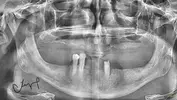

Implant tedavisi